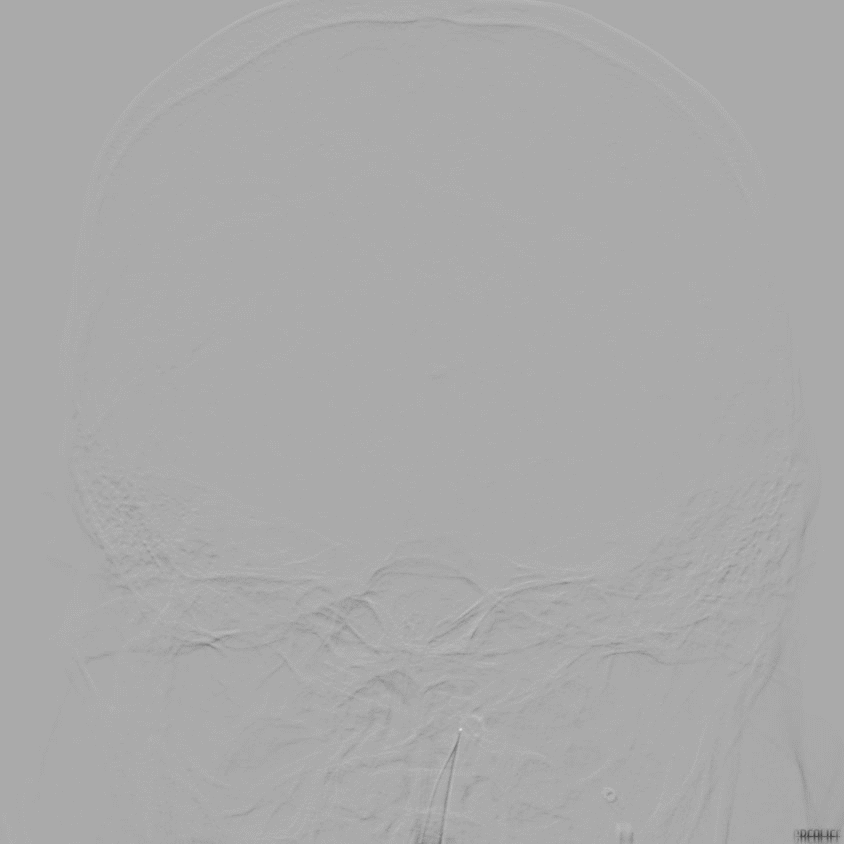

NeuroHawk Case 7